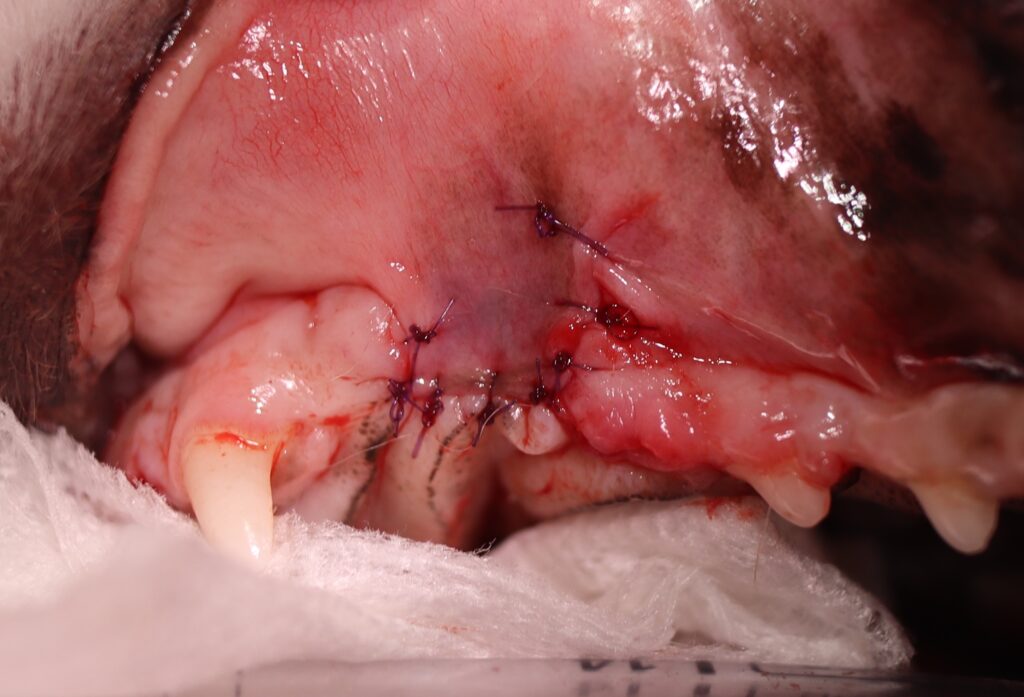

犬歯の上側の歯肉に穴が開き、内部の歯根部が露出しています。

感染源となる左上顎犬歯を完全に抜去。 - 歯肉フラップ形成

周囲歯肉を丁寧に剥離し、瘻孔を覆うように縫合閉鎖。 - 術後管理

術後は良好に経過し、瘻孔の閉鎖と症状の改善が認められました。